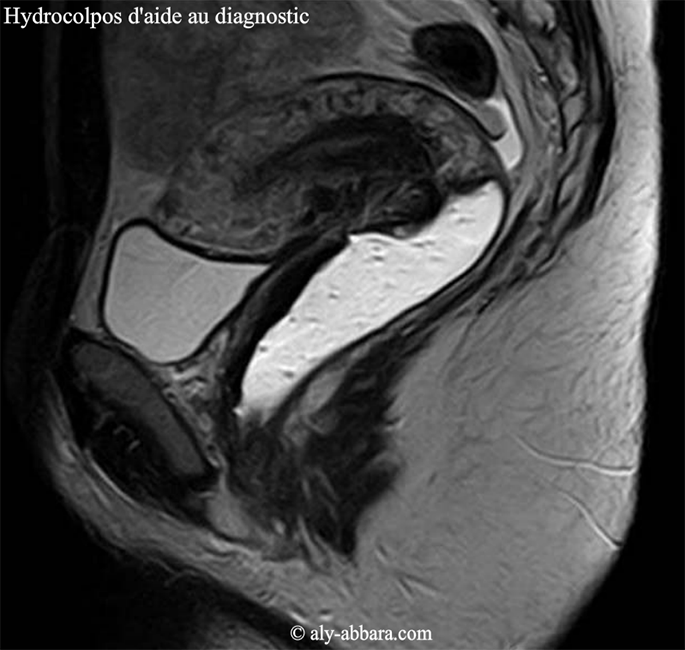

| Hydrocolpos d'aide au diagnostic | |||

| Coupe sagittale médiane du pelvis par "IRM" centrée sur un hydrocolopos créé artificiellement en injectant dans la cavité vaginale, un gel permettant la mise en évidence le vagin afin de faciliter l'interprétation des coupes anatomiques du petit pelvis. | |||